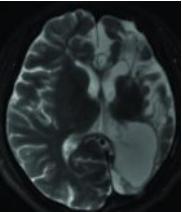

Rasmussen脑炎

Rasmussen脑炎是一种不明原因的慢性、进行性脑炎,一般多累及一侧大脑半球,或虽表现为两侧大脑受累但以一侧半球萎缩显著。

多发生于儿童,成人发病少见。

临床表现主要为局灶性难治性癫痫、部分性癫痫持续状态、进行性神经功能缺损(偏瘫、偏盲、智力下降等)。

颅脑MRI表现:一侧大脑半球萎缩性改变(脑室扩大、外侧裂和脑沟增宽、脑回变小),伴有相应部位的灰质或白质萎缩和T2WI、FLAIR高信号,深部灰质核团(尾状核和壳核)也可受累,无颅骨代偿性改变。少数早期患者可表现为暂时性局部皮质肿胀及T2WI、FLAIR高信号。